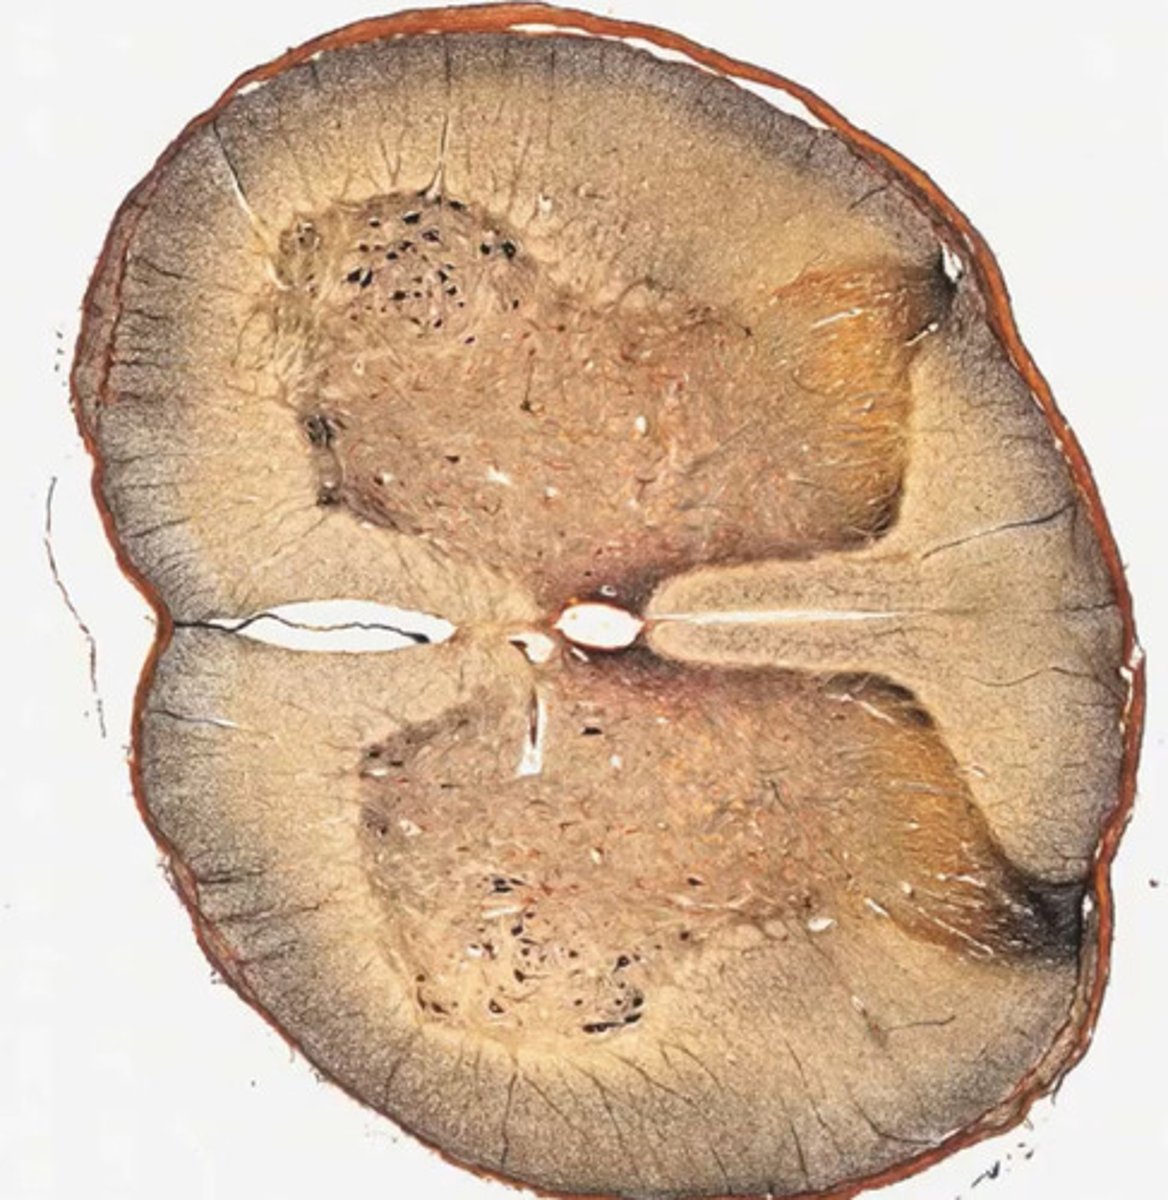

Rdzeń kręgowy (met.osmowa)